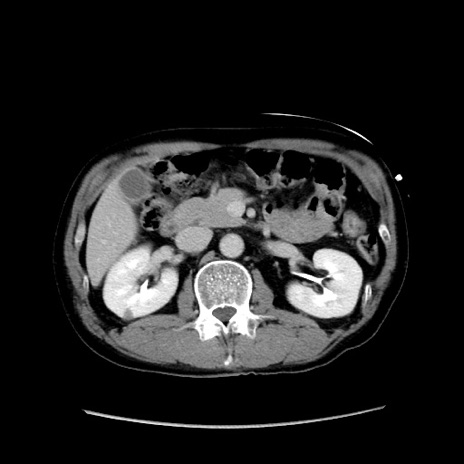

症例37(横断像)

冠状断像

【症例】40歳代 男性

【主訴】腹痛

【現病歴】4時間ほど前に電車に乗車中に臍部上より腹痛出現。徐々に増悪し起立困難となり、救急外来受診。生ものは数日食べていない。今朝お雑煮を食べた。

【身体所見】BT 36.8℃、BP 117/84mmHg、HR 91/min、SpO2 97%、苦悶様、腹部:臍上部広範囲圧痛あり、反跳痛±

【データ】WBC 8100、CRP 0.03